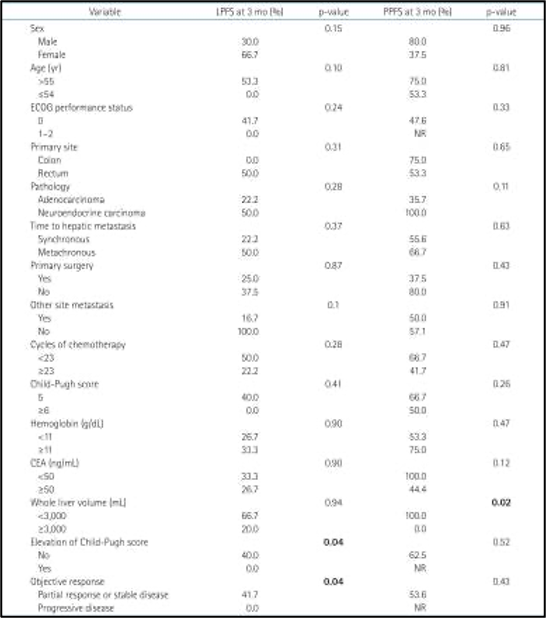

לאחר 3 חודשים, ההישרדות ללא התקדמות מקומית (LPFS) הייתה 30% וההישרדות ללא התקדמות כאב (PPFS) הייתה 58.3%. גורמים פרוגנוסטיים אפשריים הקשורים לשיעורי ההישרדות נמצאים בטבלה 3. עלייה בדירוג צ'יילד-פו (Child-Pugh score) (p = 0.04) (איור 5A) בחודש אחד לאחר טיפול קרינתי לכל הכבד (WLI) עם היפרתרמיה היה גורם פרוגנוסטי משמעותי להישרדות ללא התקדמות מקומית (LPFS). הישרדות ללא התקדמות מקומית (LPFS) נוטה להיות גבוהה יותר במטופלים ללא גרורות חוץ-כבדיות משולבות (combined extrahepatic metastasis) (p = 0.1) (איור משלים 1).

להלן איור 5: עקומות ההישרדות של קפלן-מאיר בהתאם לגורמים פרוגנוסטיים מובהקים. (A) עלייה בדירוג צ'יילד-פו (CP) בחודש אחד על ההישרדות ללא התקדמות מקומית (LPFS), (B) נפח כבד שלם (Whole liver volume) גדול מ-3,000 מ"ל המייצג נפח גידול גרורתי על ההישרדות ללא התקדמות כאב (PPFS)

להלן טבלה 3: גורמים פרוגנוסטיים אפשריים בעבור הישרדות ללא התקדמות מקומית (LPFS) וההישרדות ללא התקדמות כאב (PPFS)

נפח כבד שלם (Whole liver volume) גדול מ-3,000 מ"ל (p = 0.02) (איור 5B), אשר ייצג בעקיפין נפח גידול גרורתי (metastatic tumor volume), היה קשור באופן מובהק להישרדות ללא התקדמות כאב (PPFS) נמוכה יותר. הישרדות ללא התקדמות כאב (PPFS) נוטה להיות גבוהה יותר במטופלים עם קרצינומה נוירואנדוקרינית (neuroendocrine carcinoma) (p = 0.11) (איור משלים 2) ורמה ראשונית של אנטיגן קרצינואמבריוני (CEA) גבוהה מ-50 ננוגרם/מ"ל (p = 0.12) (איור משלים 3). תגובה אובייקטיבית (Objective response) לאחר חודש אחד לא הייתה קשורה להישרדות ללא התקדמות כאב (PPFS) (p =0.43).